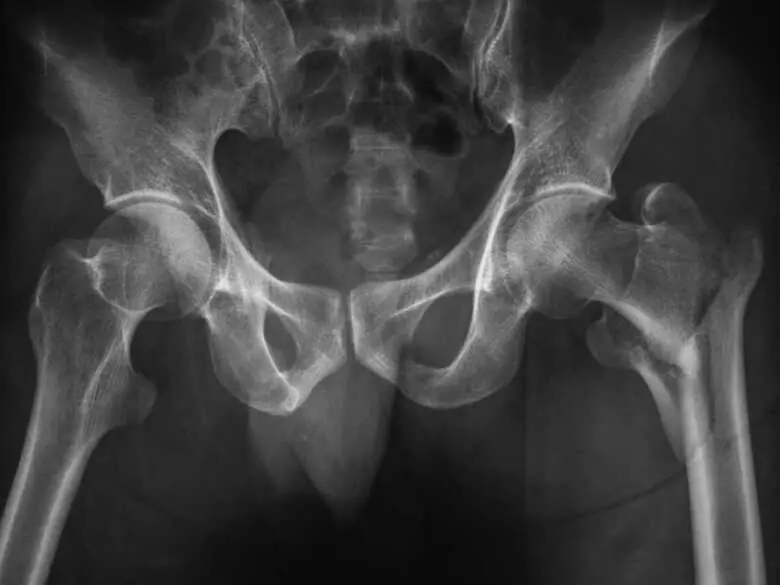

Photo de rayons X hanches